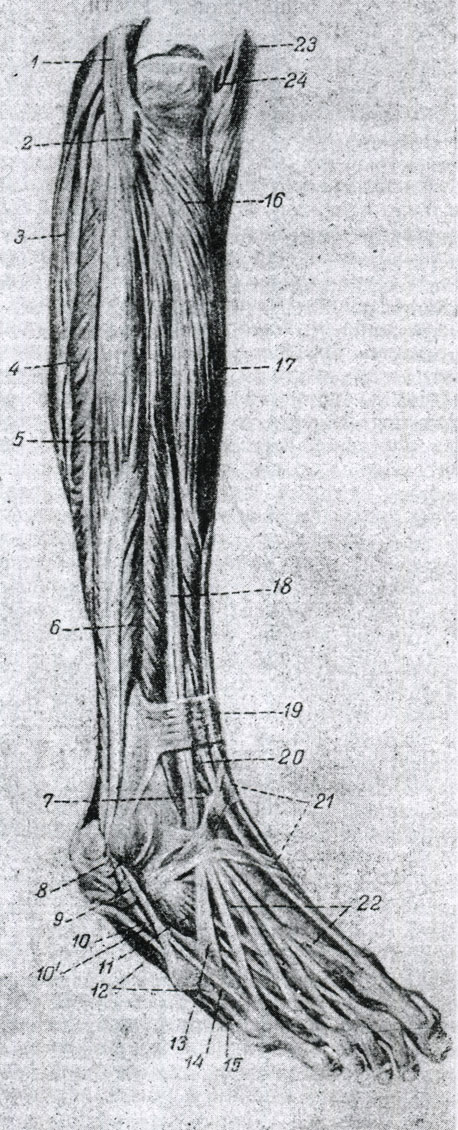

Анатомия голеностопа: Сухожилия и их строение